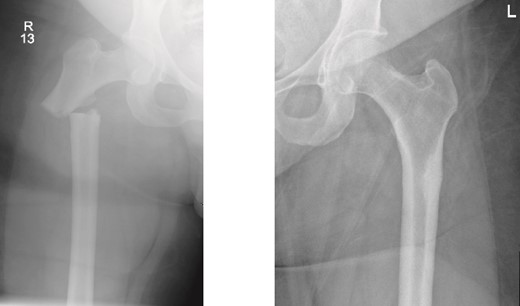

On examination, the patient was alert, oriented, and vitally stable. There were no open wounds on the right thigh, but mild tenderness was noted. The soft compartments were palpable, and the ankle range of motion was full. Distal neurovascular structures were intact. The left thigh showed no wounds or tenderness, and the hip range of motion was 0° to 60°, limited by pain in the right hip, as reported by the patient. Distal neurovascular structures were also intact on the left side. X-rays of both the right and left femurs, taken in the emergency department, are shown in Fig. 1.

Anteroposterior (AP) view of the right and left femurs pre-operative. With ismuths of 7.7 in R and 6.9 in L

Surprisingly, as seen in the X-rays in Fig. 1, the patient had a right subtrochanteric femur fracture and a stress line in the contralateral femoral cortex. While preparing and optimizing the patient for surgery, the endocrinology team was consulted regarding this presentation. According to their assessment, the patient’s laboratory findings were reassuring, and they confirmed that we could proceed with the surgical plan. Bone mineral density (BMD) testing was planned for afterward, and the endocrinology team would review the results. Surgery was scheduled for the following day.